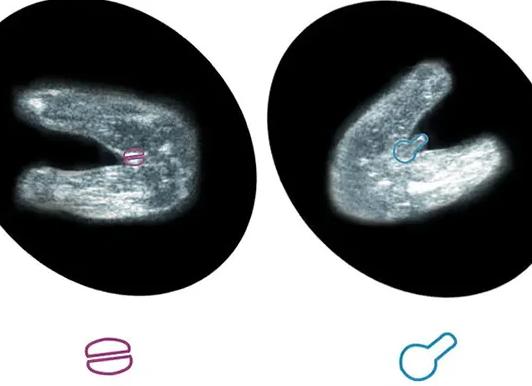

- отсутствие овуляции;